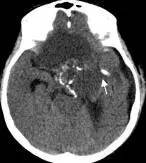

病例1:患儿男性,9岁。因反复出现意识丧失、视力降落半年收入院。入院后CT及 MRI显示颅内有形态不规则、“超大型”的颅咽管瘤,最大径约10厘米,见图1、图2。

图1.术前CT显示典型的囊性颅咽管瘤